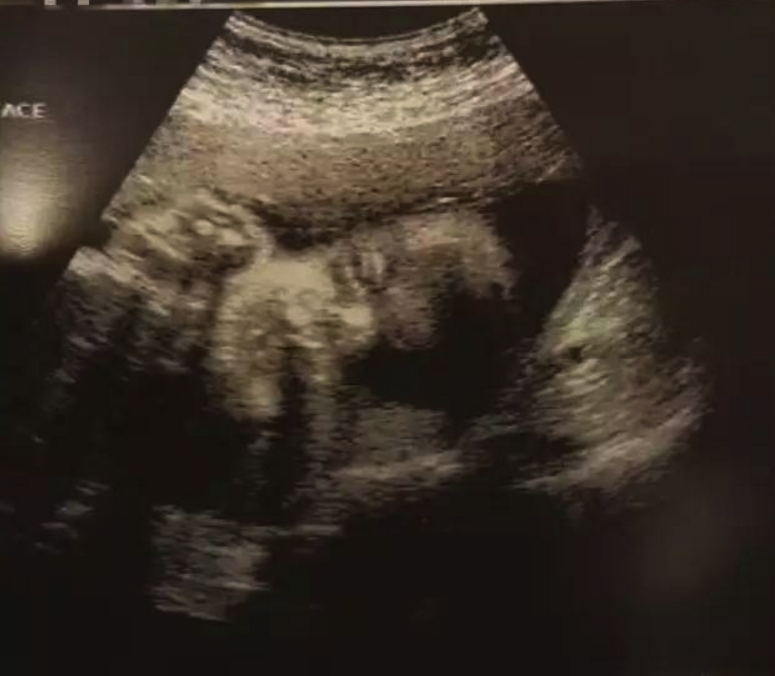

從2004年到2016年,我12年的奮戰(zhàn)史終于成功了,為了呵護好腹中的孩子,我決定在美好好安胎,等三個月穩(wěn)定后再回國。8月22日,我去診所做了B超,醫(yī)生微笑著告訴我,已有胎心搏動,想著腹中還有另外一個小人兒的心跳,我的內(nèi)心就激動。原本以為這一生都不會懷孕,沒成想,在多年的堅守后,我還能懷自己的孩子。并且,我的醫(yī)生告訴我,懷孕和生產(chǎn)對于腺肌癥是有好處的,我還要感謝我的孩子,為我驅(qū)走病痛的折磨。